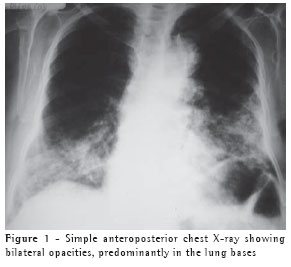

Imaging studies were carried out (Figures 1 and 2). The patient history included antireflux surgery for gastroesophageal reflux disease twelve years prior, in addition to a long history of intestinal constipation. She was an inveterate user of laxatives. She had been a two-pack-a-day smoker for 50 years, having quit smoking four months prior to seeking treatment. She had kept two canaries in her house for the last ten years.

Simple X-rays show basal opacities, diffuse opacities or, occasionally, a solitary low-density mass known as paraffinoma.(5) High-resolution computed tomography scans reveal consolidation with low attenuation, ground-glass opacity or a mosaic pattern of attenuation,(1,5-8) as was reported in the present case.